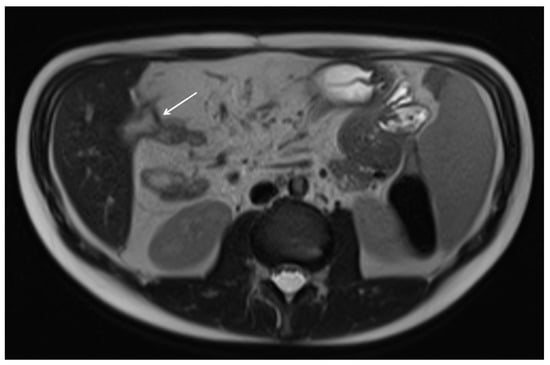

10. Imaging Findings Associated with Active CD Inflammation

Segmental mural hyperenhancement

| Engorged vasa recta |

| Mesenteric venous thrombosis and/or occlusion |